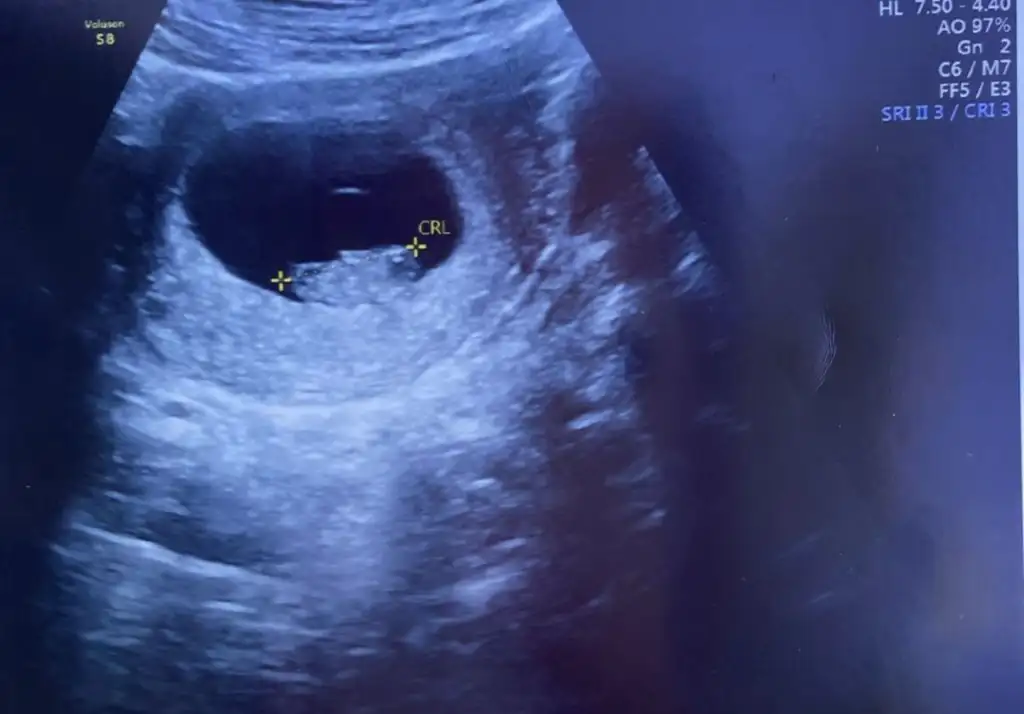

31 yaş. İlk gebelik, Hatay. Kız hissediyorum . Sat 17 Mart. Keseyi 5+3 te gördük. Kalp için yarın gidicem 7+4 olacakKızlaaaaaaarrrrrrrrr,

Hayırlı olsunn, ekledim :)31 yaş. İlk gebelik, Hatay. Kız hissediyorum . Sat 17 Mart. Keseyi 5+3 te gördük. Kalp için yarın gidicem 7+4 olacak

Kızlar cinsiyet tahmini var mı :) Kız hissediyorum ben

Canım aynı tarih kalp atışını duydun mu33 yaşındayım. 2. çocuk. istanbuldayım. 7. hafta keseyi görmeye gittim. SAT 20 mart. tahmini doğum 25 aralık![]()

yok sadece gördüm bugün. haftaya kalp atışını dinleriz dediCanım aynı tarih kalp atışını duydun mu